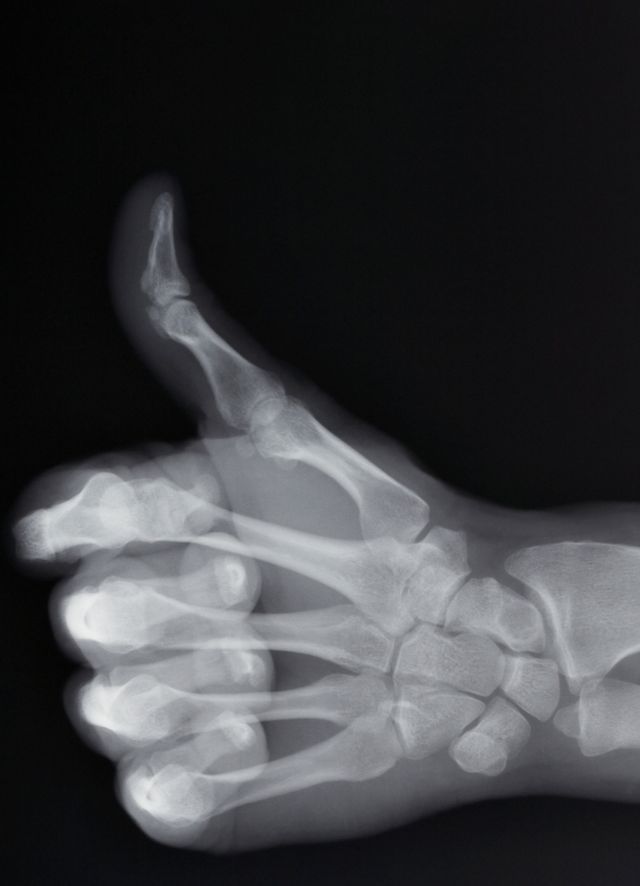

Herr Bley, Röntgenstrahlung kann zwar bei der Diagnose verschiedenster Krankheiten helfen, für den Körper kann sie aber auch schädlich sein. Warum eigentlich?

Bley: Röntgenstrahlen sind energiereich. Sie können, vereinfacht gesagt, kleine Teile der DNA beschädigen. Zum Glück ist der Körper ein guter Reparateur, in den meisten Fällen behebt er den Schaden selbst. Wenn er der Strahlung zu stark oder zu häufig ausgesetzt ist, kann er das nicht mehr. Im Extremfall entsteht später Krebs.